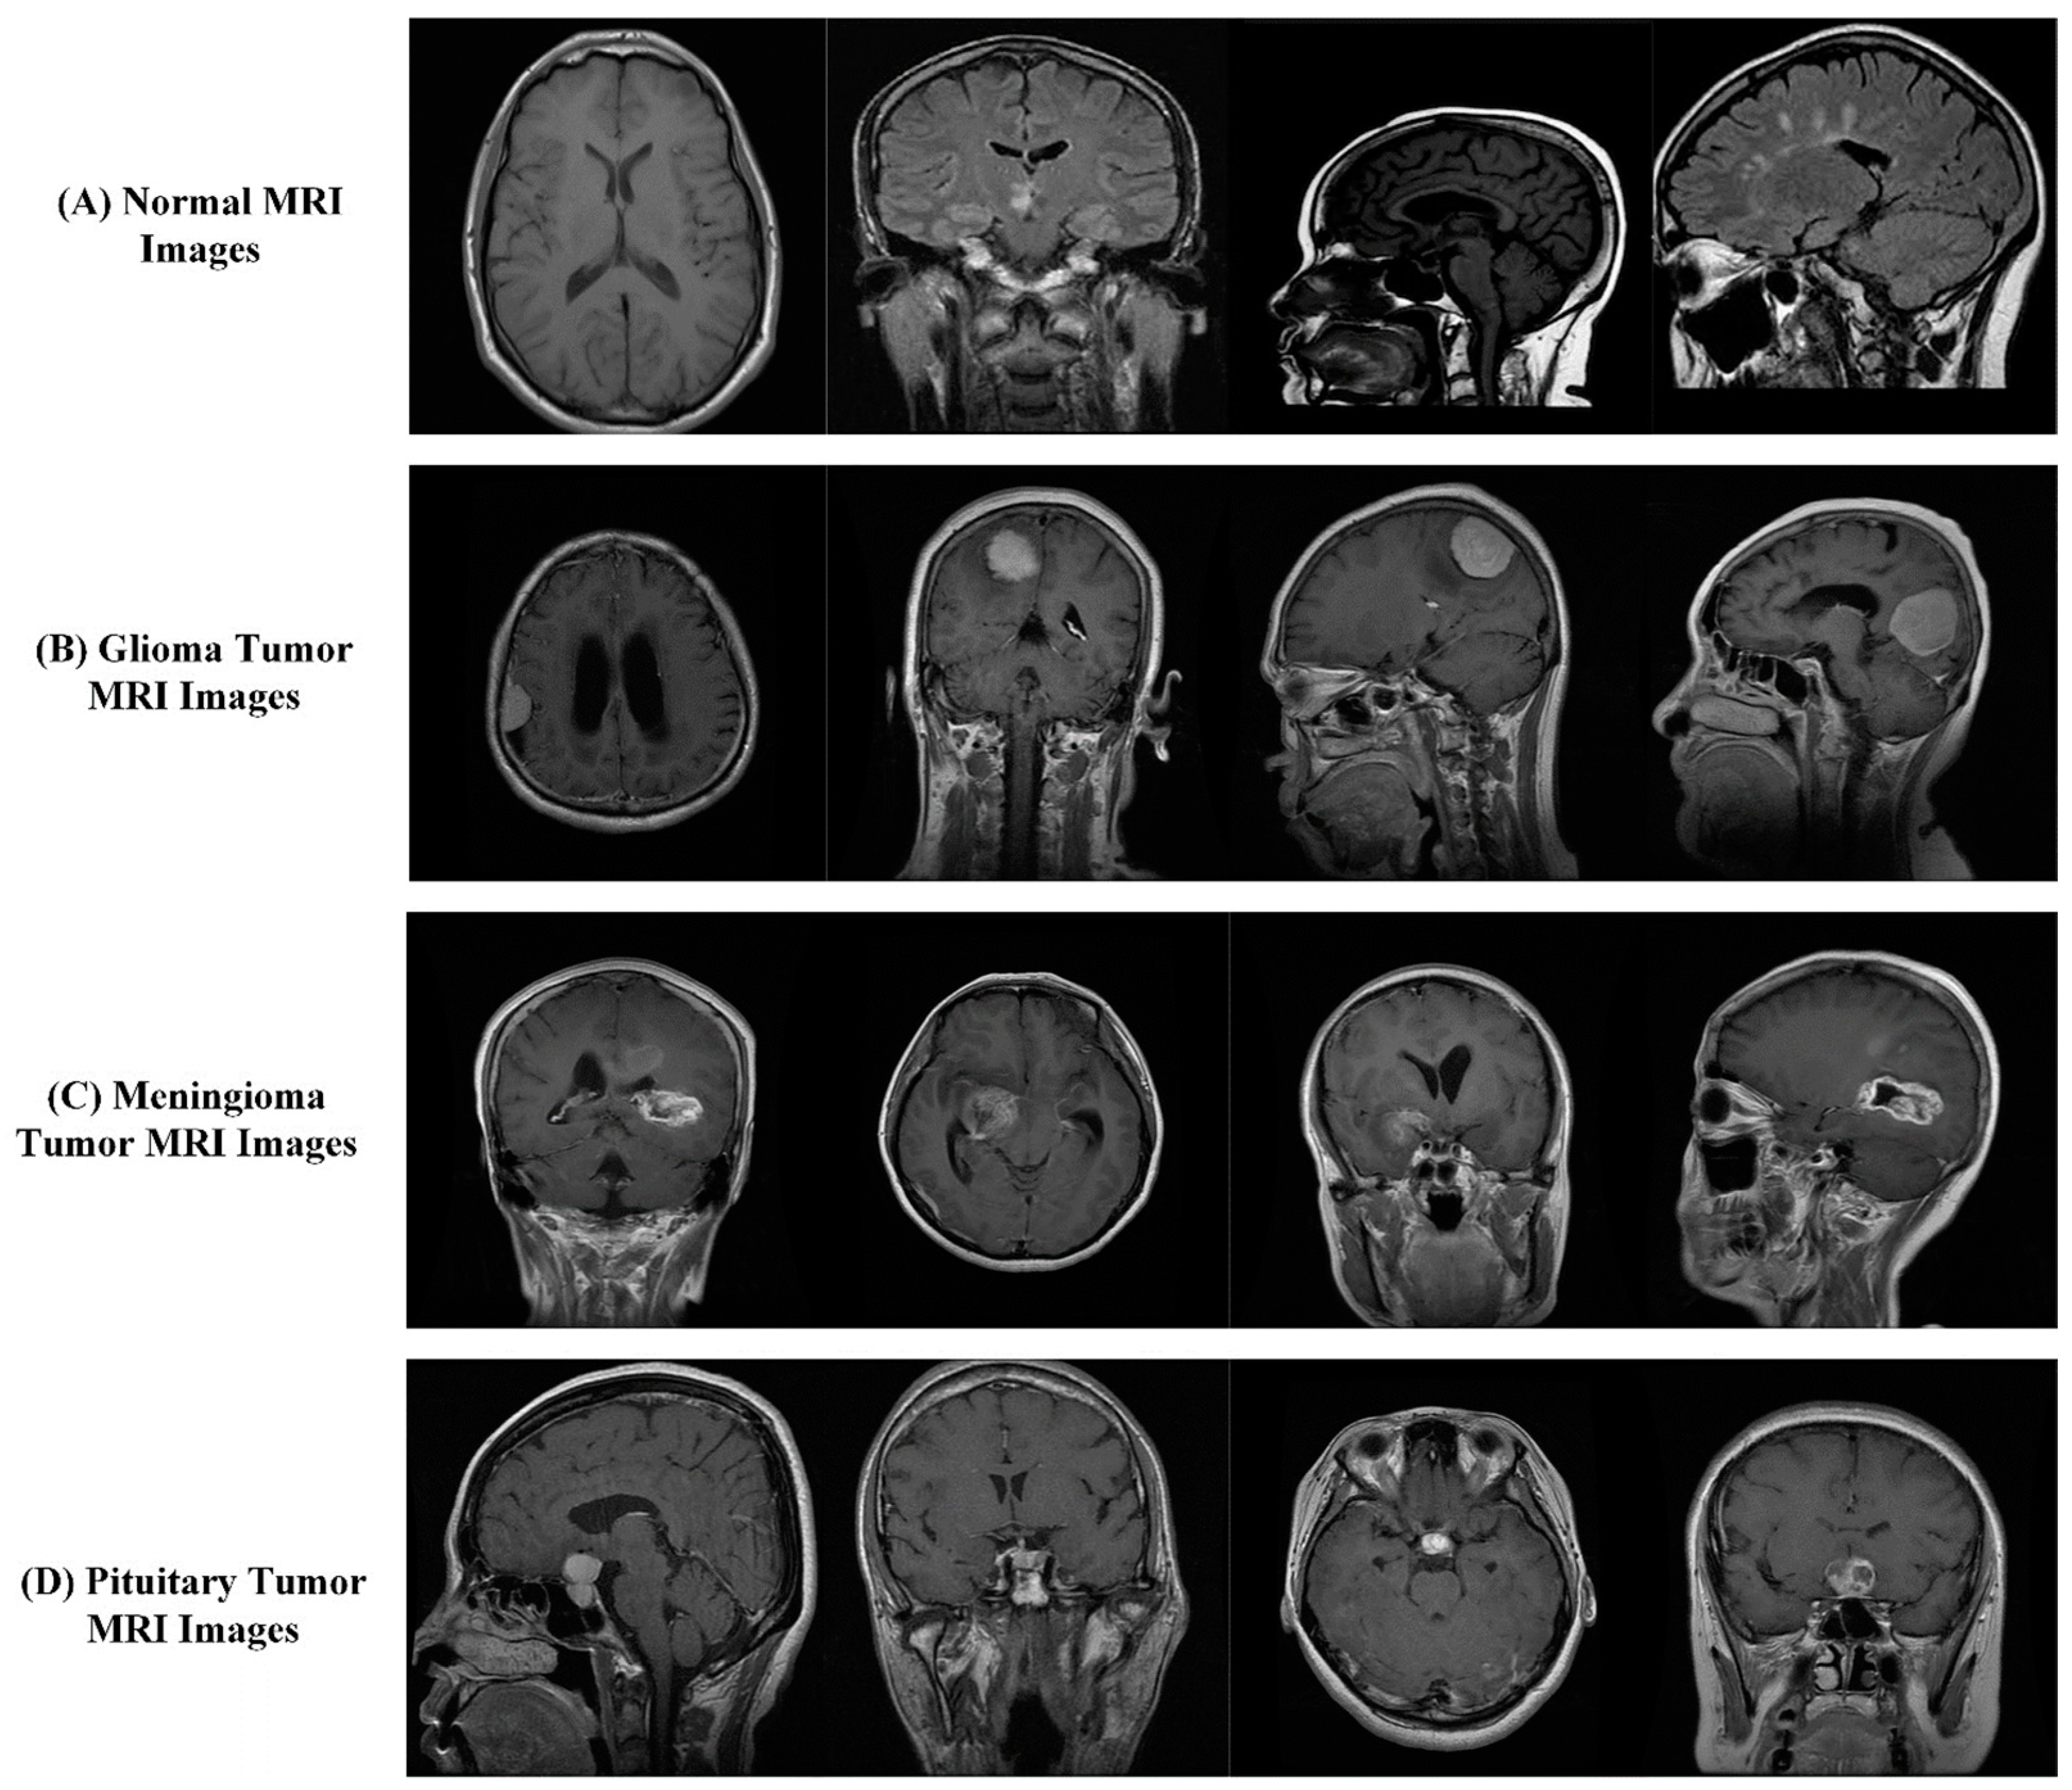

2.1. Dataset